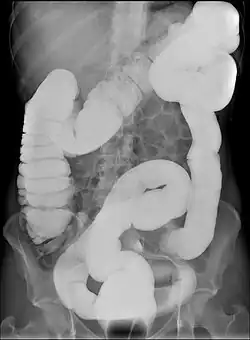

Dolicocolon

In medicina, un dolicocolon (parola derivata dal greco antico dolilchos, la lunga distanza, e colon) è un'anomalia del colon caratterizzata da un abnorme allungamento. Tale patologia è di solito congenita ma a volte può anche essere una conseguenza dell'assottigliamento e allungamento delle pareti intestinali.

Il dolicocolon colpisce prevalentemente il colon discendente ed il sigma (dolicosigma) e predispone al volvolo poiché il colon tende a ripiegarsi su se stesso con maggior facilità.[1] Spesso è ad interposizione tra il diaframma ed il fegato (vedi sindrome di Chilaiditi). Questa anomalia può essere associata ad una dilatazione del colon (dolico-megacolon) come nella malattia di Hirschsprung in cui dilatazione e allungamento sono la conseguenza di un difetto dell'innervazione della parete intestinale, che causa paralisi della peristalsi intestinale. Il dolicocolon in soggetti predisposti per via della forma del colon, può favorire formazioni di fecalomi tali da causare frequenti sub-occlusioni intestinali.

Questa anomalia è quindi spesso anche associata a stitichezza cronica, a volte anche ostinata.